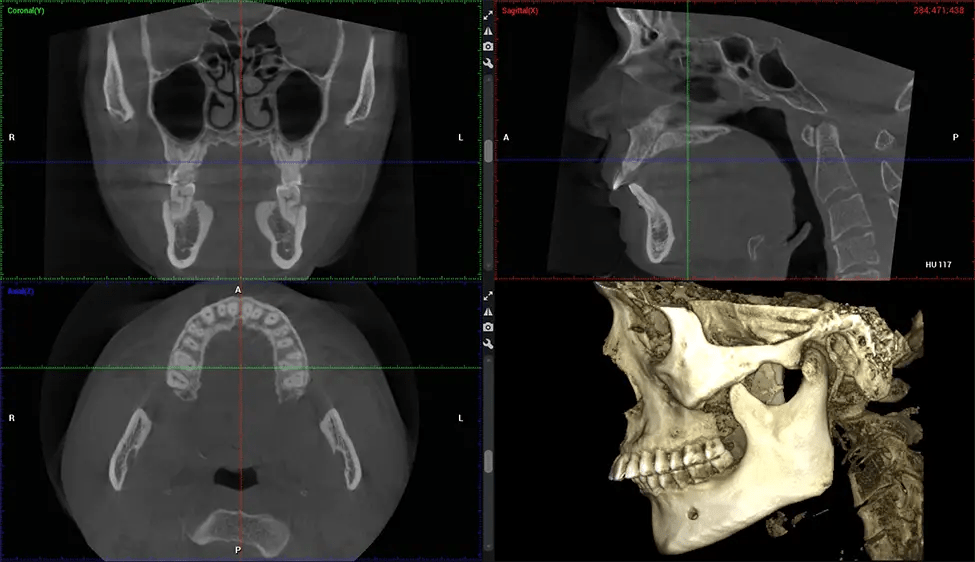

Primero se coloca al paciente en el escáner CBCT, que normalmente consta de un brazo giratorio que alberga la fuente de rayos X y un detector. La cabeza del paciente está inmovilizada para garantizar una captura de imágenes precisa. La fuente de rayos X y el detector giran alrededor de la cabeza del paciente, capturando varias imágenes de rayos X desde múltiples ángulos. A medida que la fuente de rayos X gira, emite un haz de rayos X en forma de cono hacia el detector. El detector captura las imágenes de rayos X, que luego son procesadas por el software CBCT.

Después del proceso de escaneo, las imágenes de rayos X capturadas son procesadas por el software CBCT, que aplica algoritmos para reconstruir una imagen 3D detallada del área escaneada. El software recopila estas imágenes de rayos X individuales y crea una representación digital en 3D de la anatomía del paciente. El dentista o el radiólogo pueden ver y analizar la imagen CBCT 3D reconstruida. Esta imagen se puede manipular, rotar y acercar o alejar para examinar estructuras específicas y evaluar la condición del paciente.

Planmeca Viso G7 CBCT (Cone Beam CT Scan) está diseñado para superar las demandas de los líderes de la industria, los especialistas y las grandes instituciones. Tiene un gran sensor de ø25×30 cm con cuatro cámaras integradas. Puede capturar tamaños de volumen ilimitados, desde ø3×3 cm hasta ø30x30cm, capturando el casquete escutelario a través de C7 en la columna cervical. Planmeca Viso G7 ofrece el escaneo de volumen único más grande de la industria de ø30×19 cm. Está preparado para manejar modalidades de imágenes avanzadas como la tecnología Planmeca ProFace® y Planmeca 4D™ Jaw Motion. El soporte occipital para la cabeza permite una visión sin obstáculos del tejido facial.